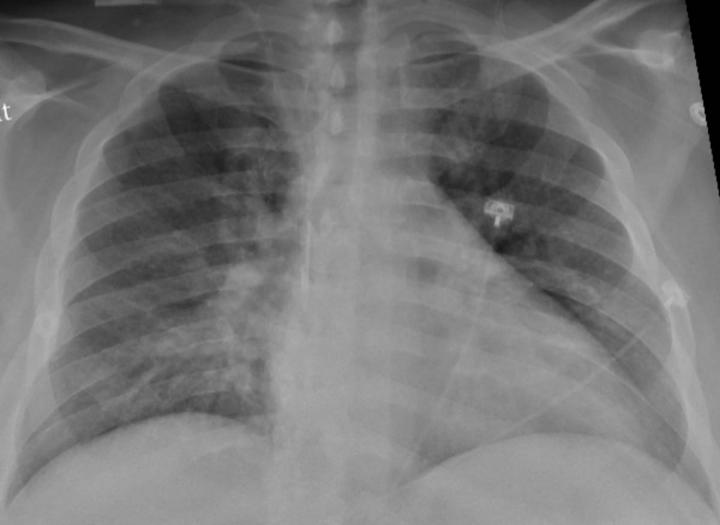

image: Chest X-ray of a SARS-CoV-2-positive patient exhibiting confusion and showing weakness on his left side shows pneumonia in the lower lungs.

The virus that causes COVID-19 first attacks cells in the respiratory system, often leading to an inflammation of the lungs that puts people at risk of contracting pneumonia. But the virus' impact has also been felt in other systems of the body.